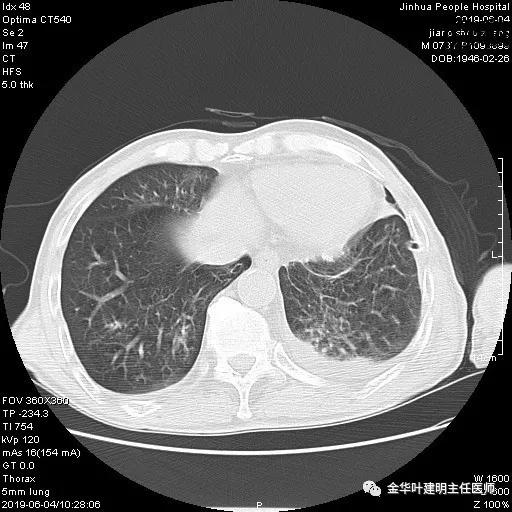

考虑左侧大量胸腔积液,遂进一步胸部CT检查:

以上是肺窗表现,下面为纵隔窗影像: